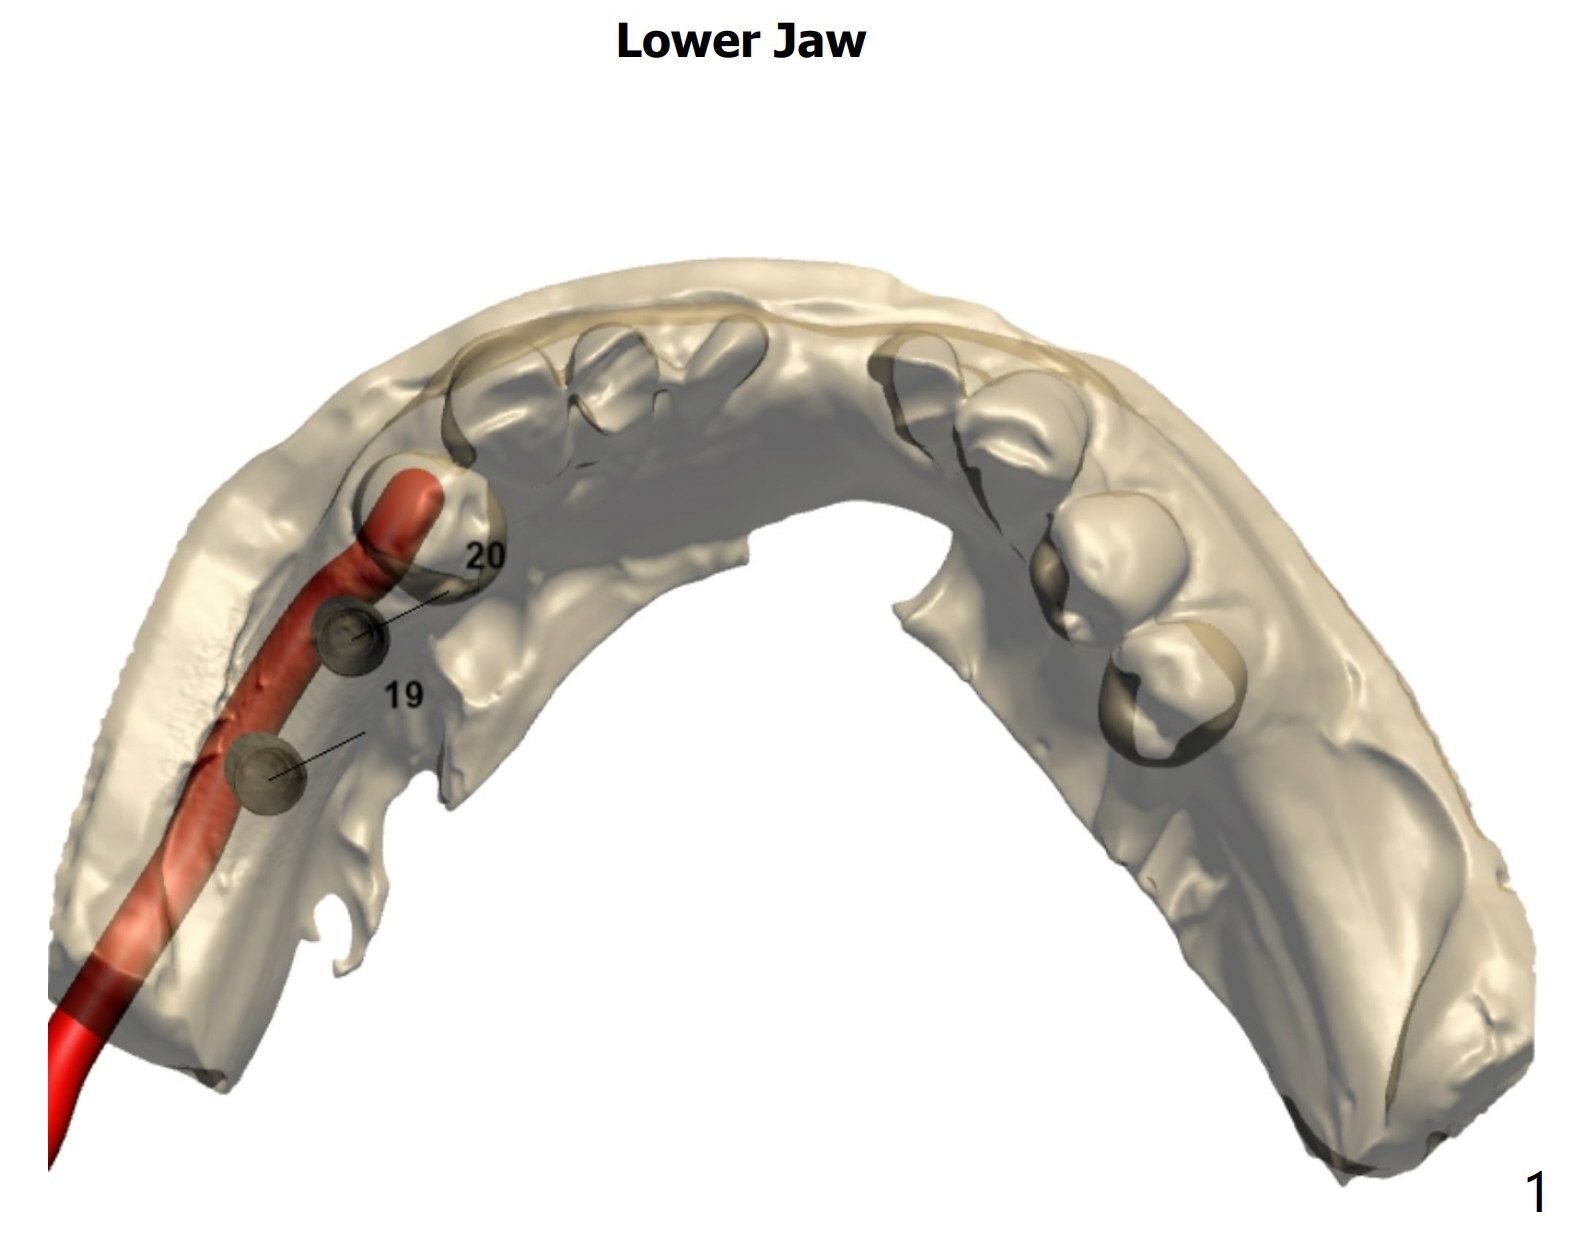

1-P, 2-P, Guide and Free Hand